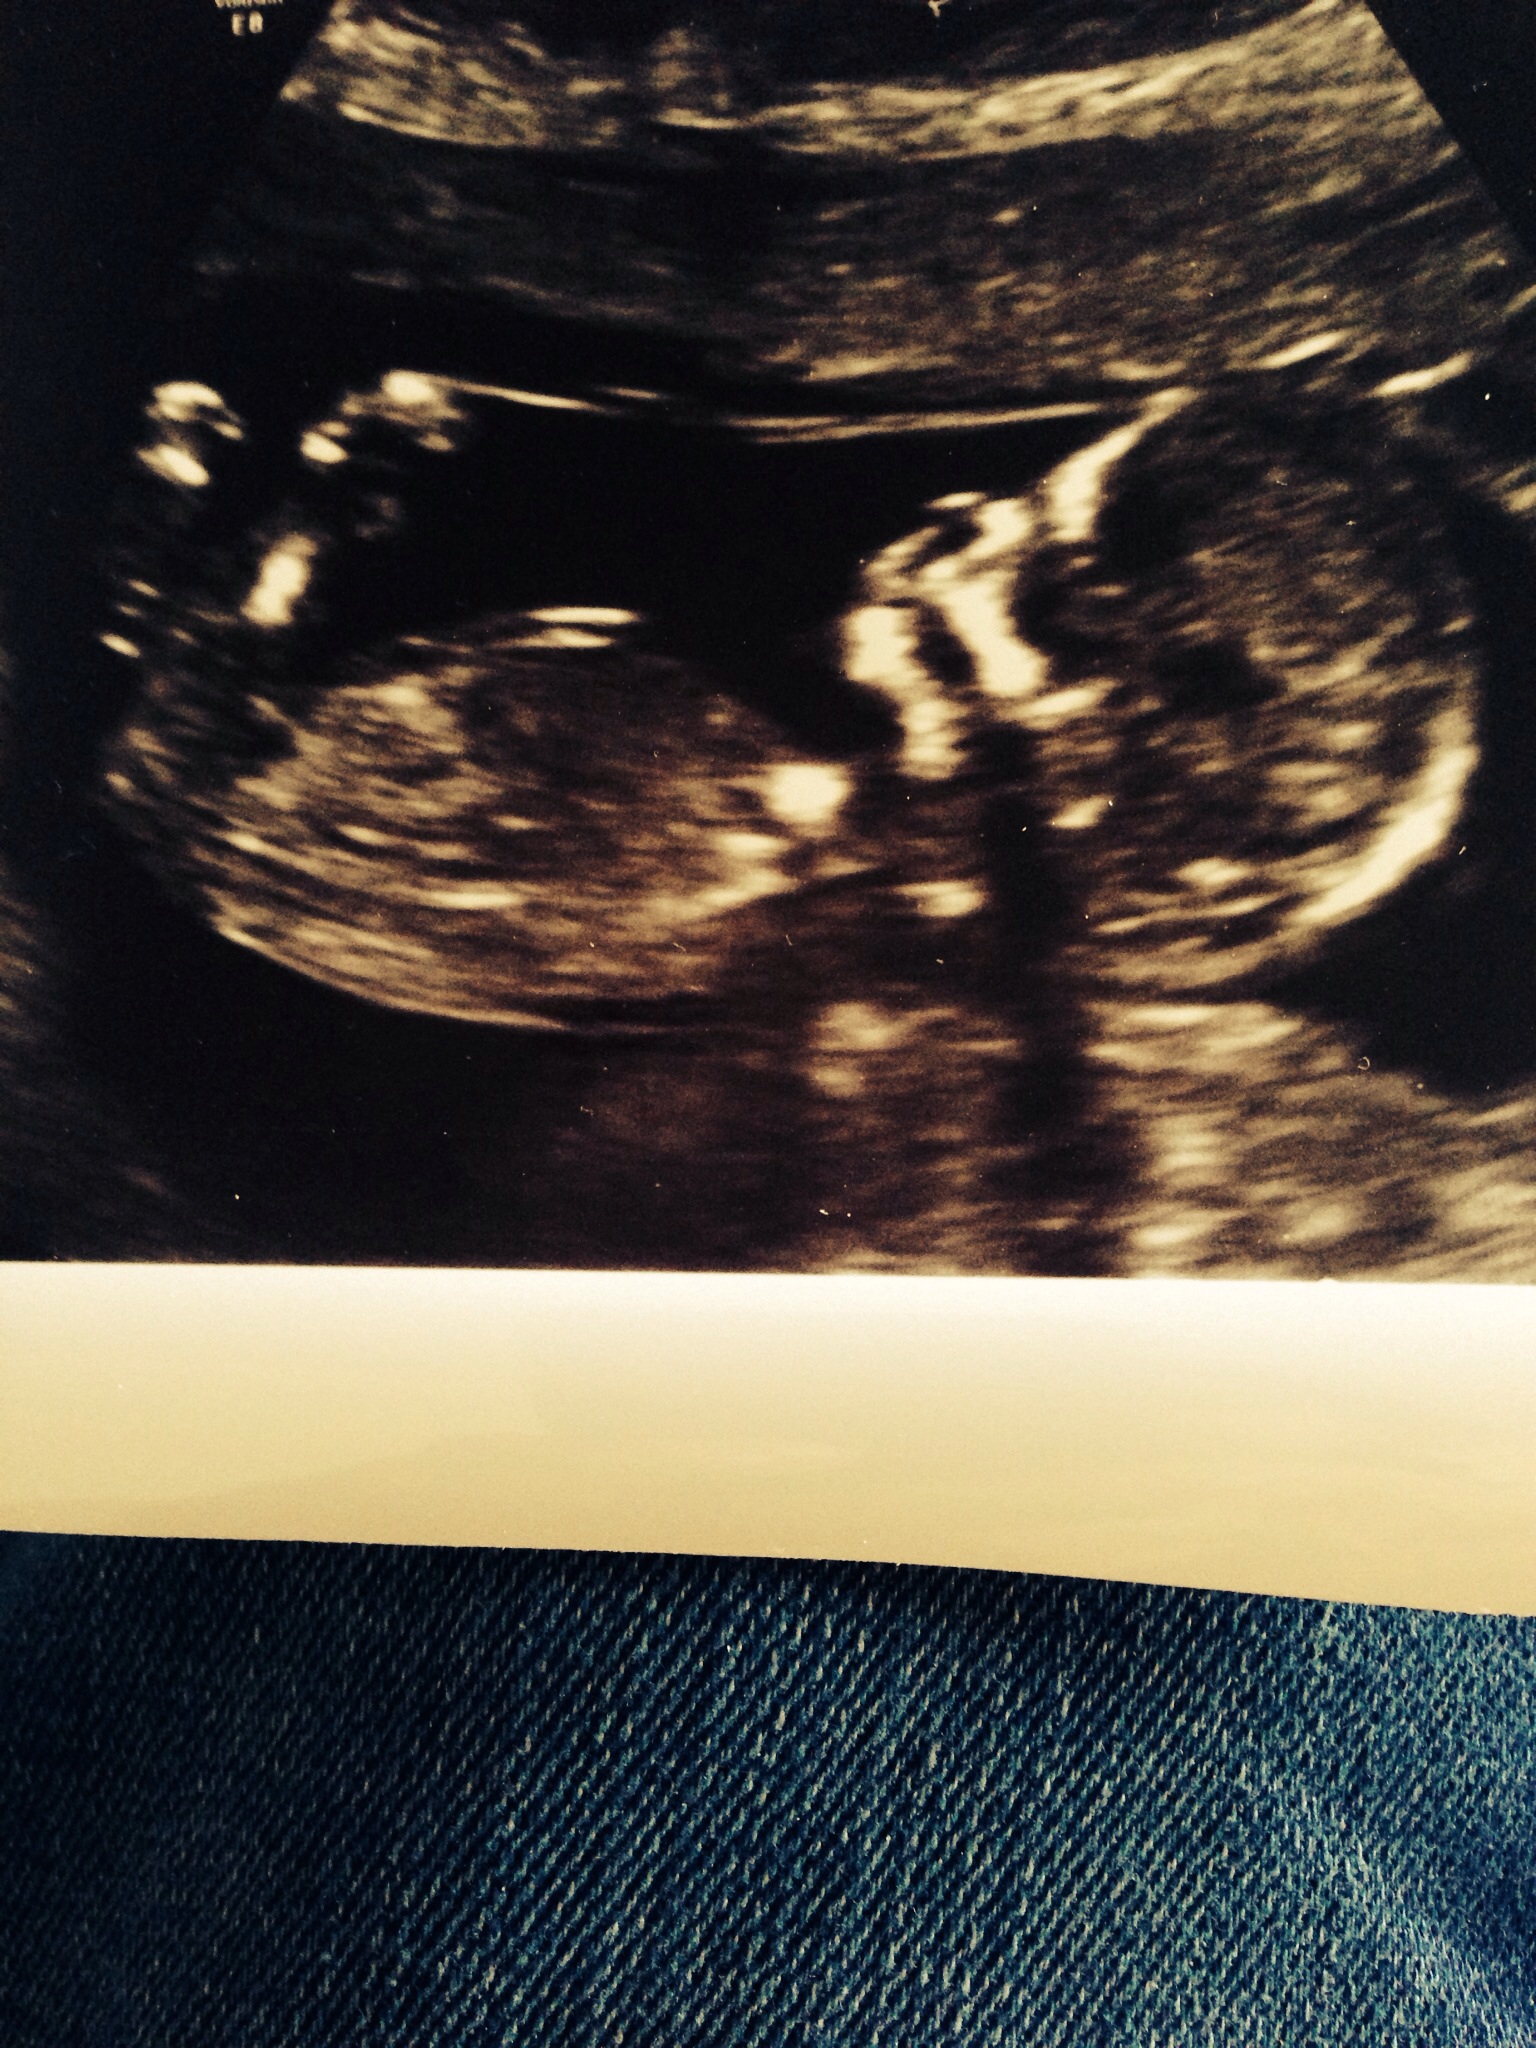

13 weeks, what is gender? Attachment 19773

Not too sure. I could see it go either way...it's not very clear in that area.

Idk if I'm seeing the nub but if it is the nub I'm looking at then I'd guess boy

50/50 for me too, but congrats on the sweet baby!!!

Boy